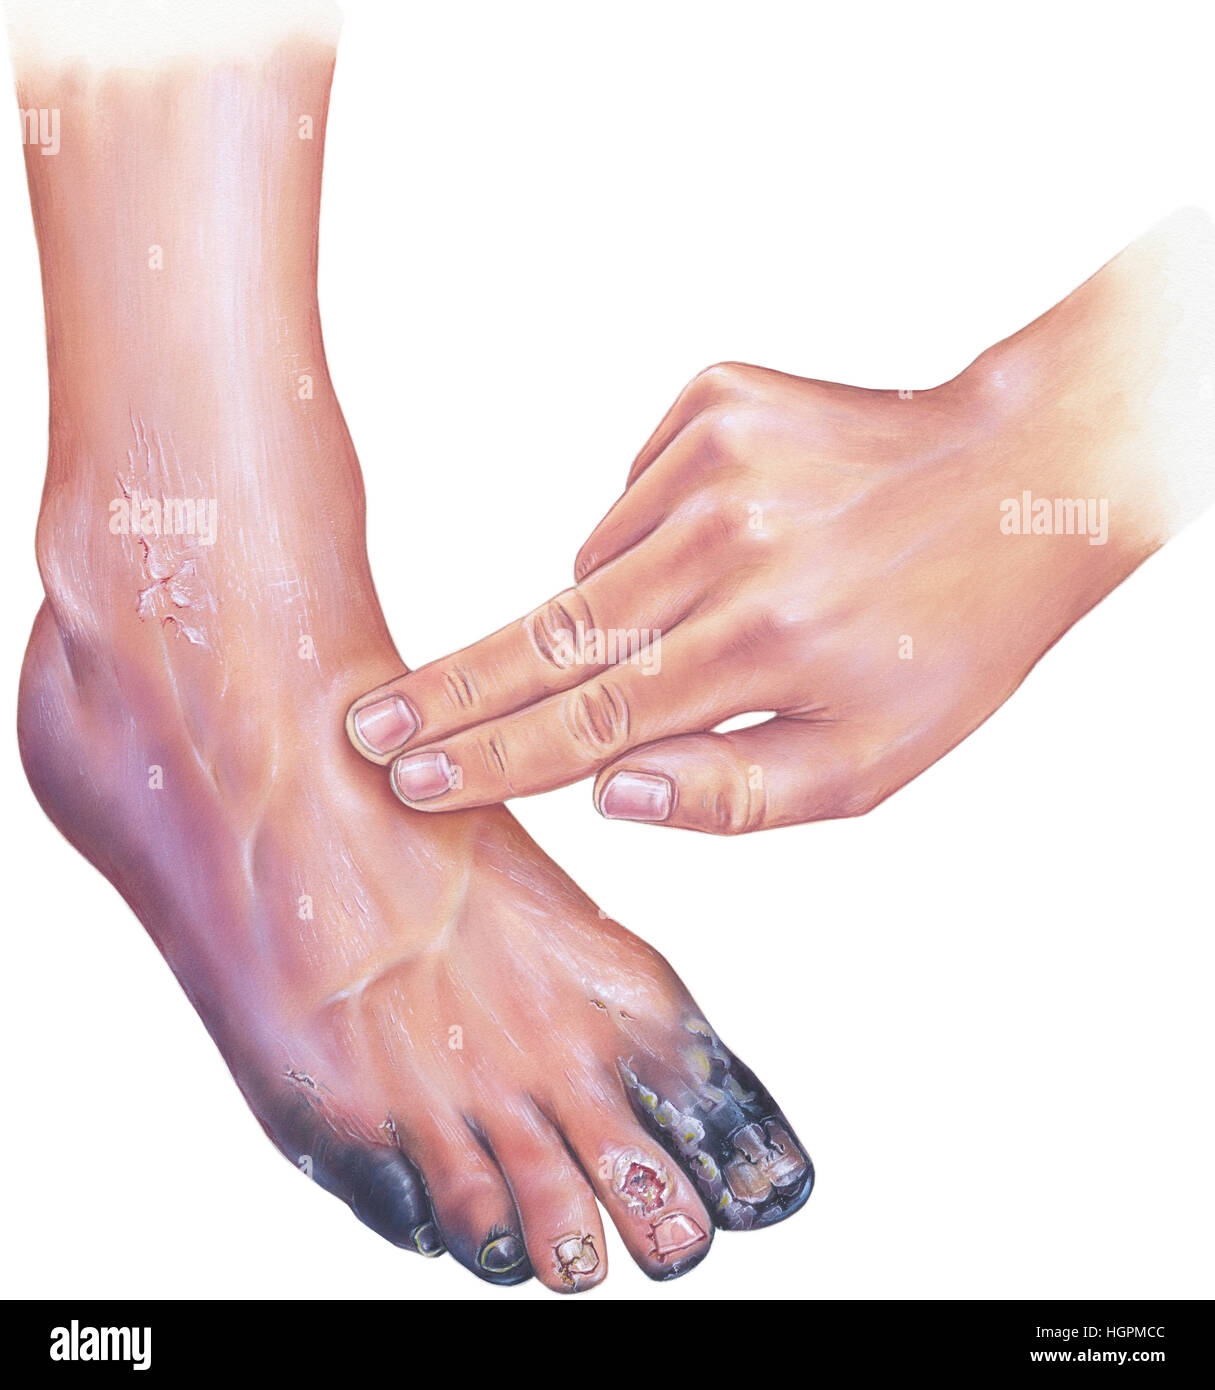

Diabetic arterial disease, showing gangrene and ulcerations of the toes. Although it is unusual in other atherosclerotic peripheral vascular diseases, Stock Photohttps://www.alamy.com/image-license-details/?v=1https://www.alamy.com/stock-photo-diabetic-arterial-disease-showing-gangrene-and-ulcerations-of-the-130806044.html

Diabetic arterial disease, showing gangrene and ulcerations of the toes. Although it is unusual in other atherosclerotic peripheral vascular diseases, Stock Photohttps://www.alamy.com/image-license-details/?v=1https://www.alamy.com/stock-photo-diabetic-arterial-disease-showing-gangrene-and-ulcerations-of-the-130806044.htmlRFHGPMCC–Diabetic arterial disease, showing gangrene and ulcerations of the toes. Although it is unusual in other atherosclerotic peripheral vascular diseases,